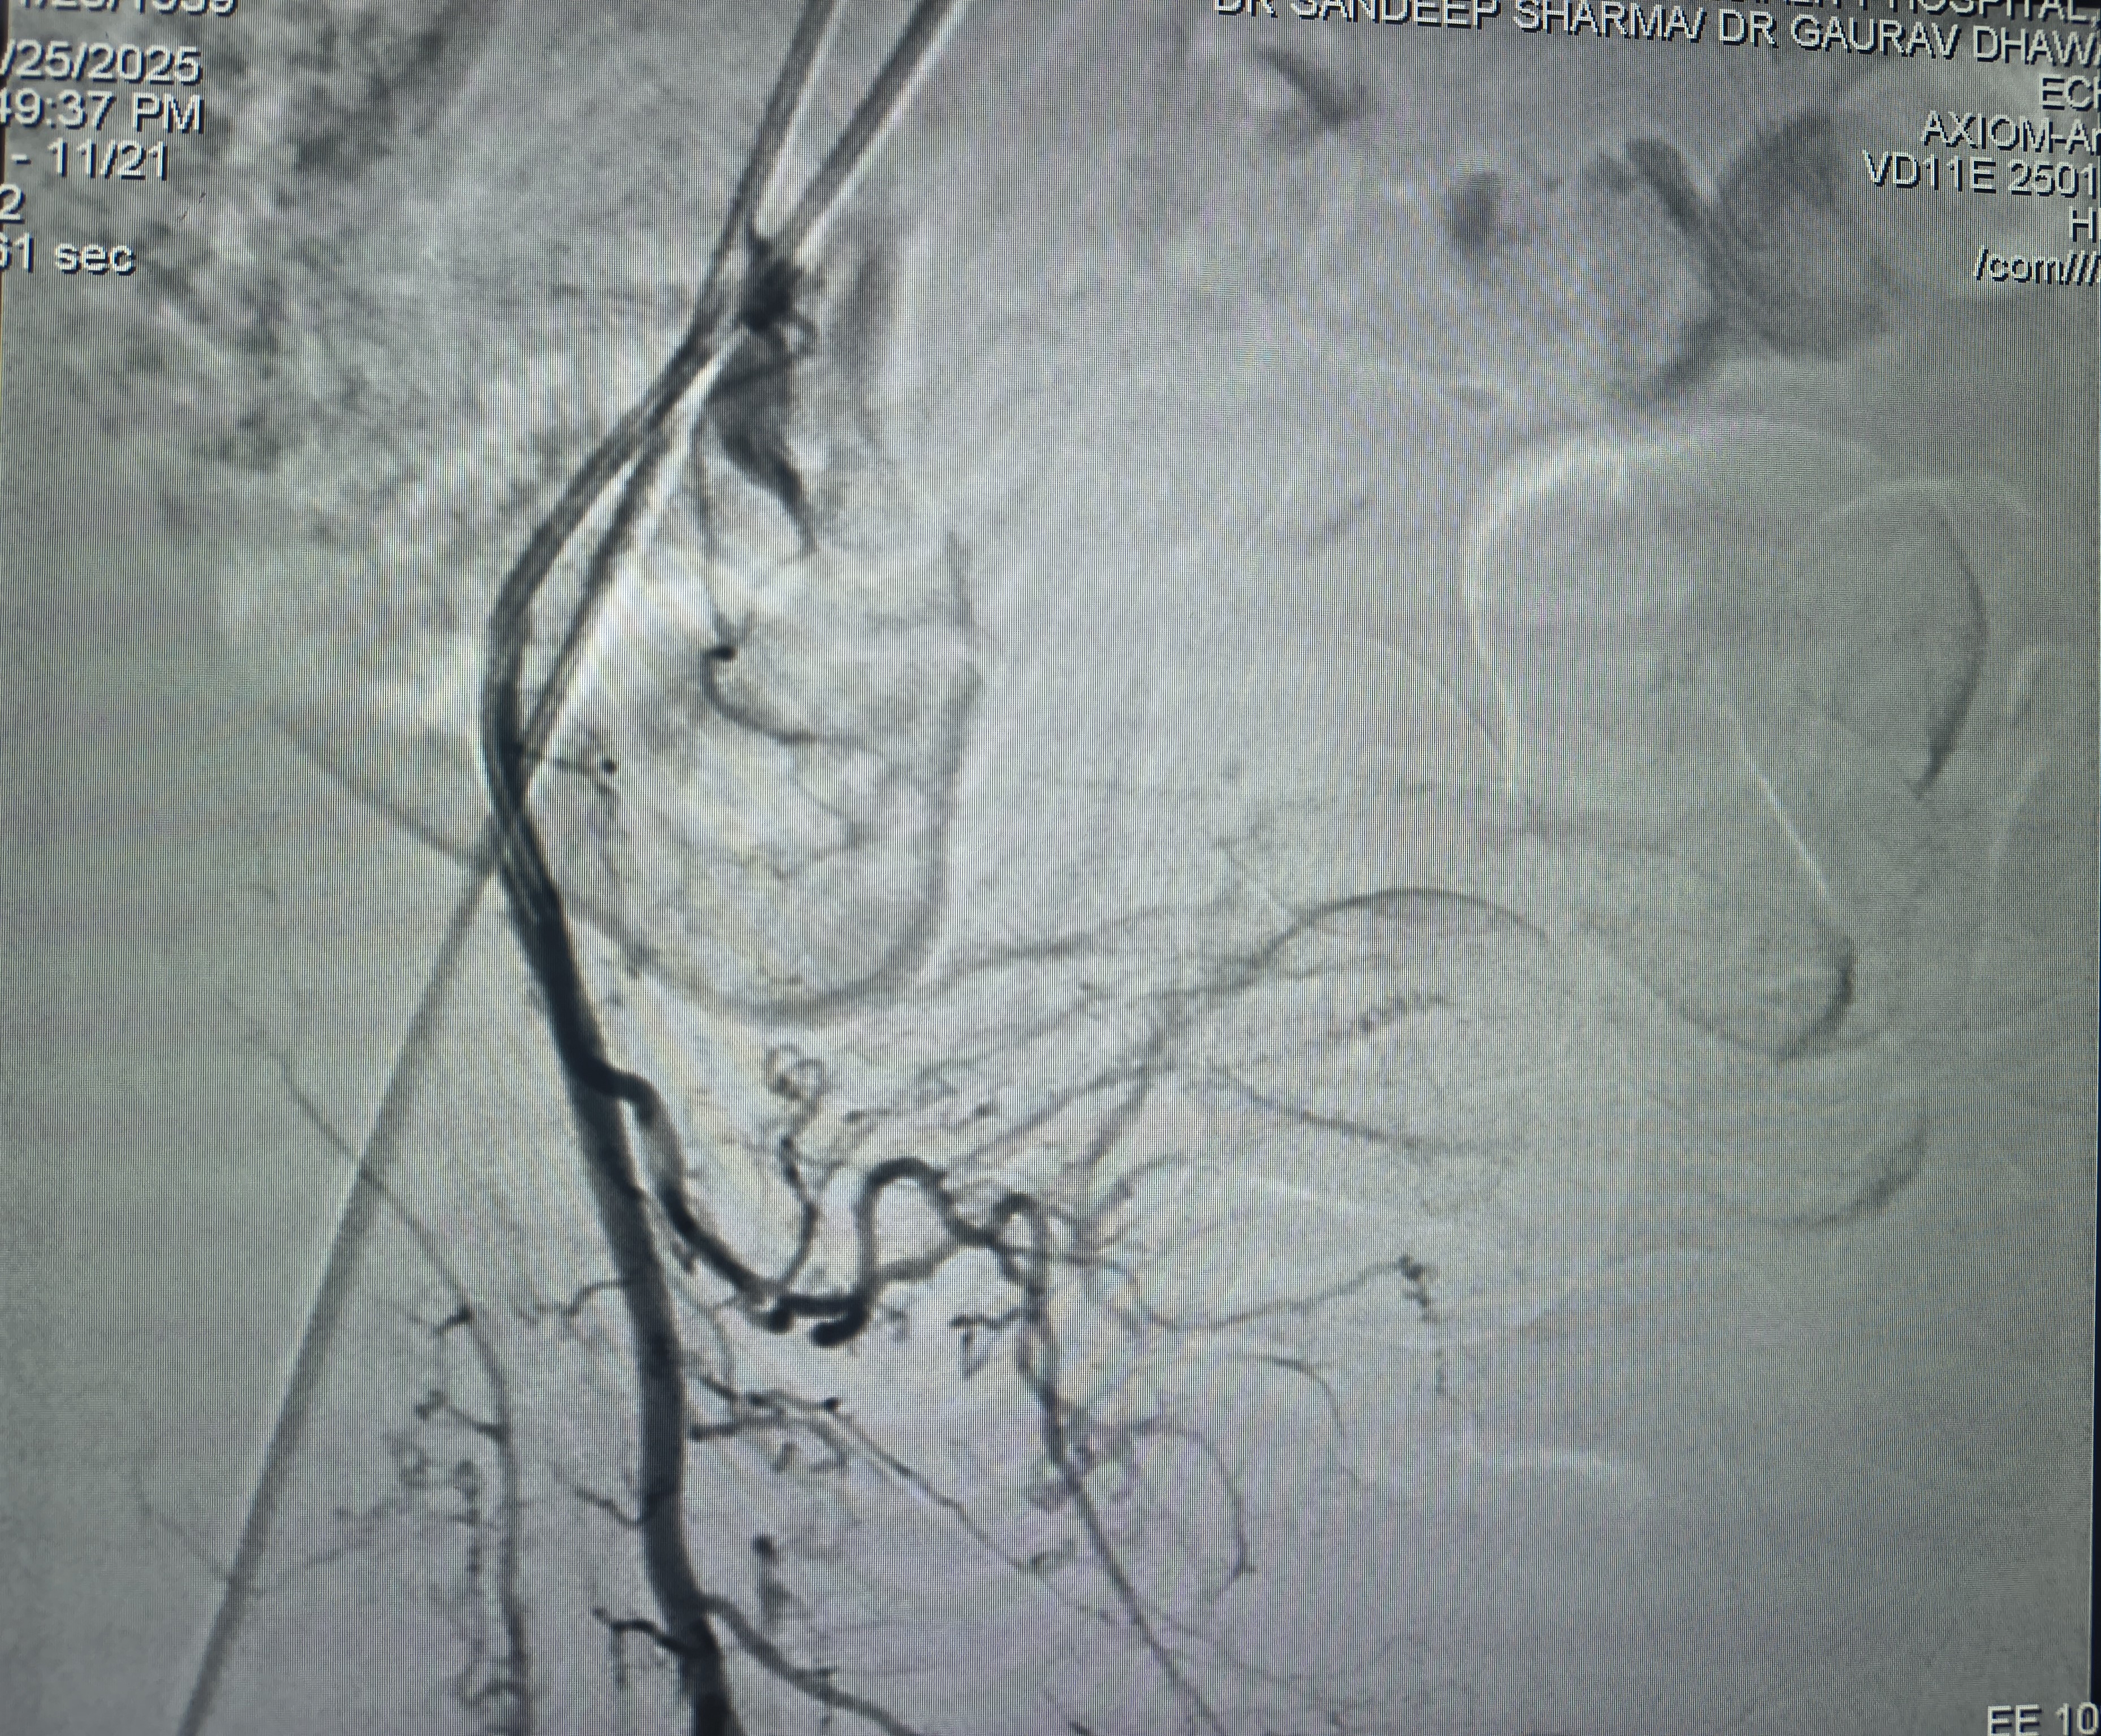

AVM embolisation